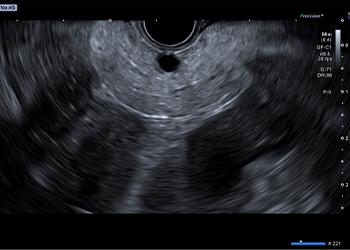

The Aplio i800 EUS ultrasound system’s innovative imaging technology provides clarity, depth, and detail. Clear imaging with high-resolution and deep penetration, as well as an abundance of imaging technologies, allow you to safely perform the procedure and diagnosis confidently.

- Differential THI (D-THI): Expands the effective bandwidth by transmitting a combined pulse with two different frequencies to simultaneously achieve increased penetration as well as high resolution with sensitivity in both superficial and deep regions compared to other THI methods.

- Full Focus: Enables clear, uniform images from near and to far field without the need for focus adjustments.

- Quick Scan: An automatic gain adjustment that provides a uniform image with just one click.